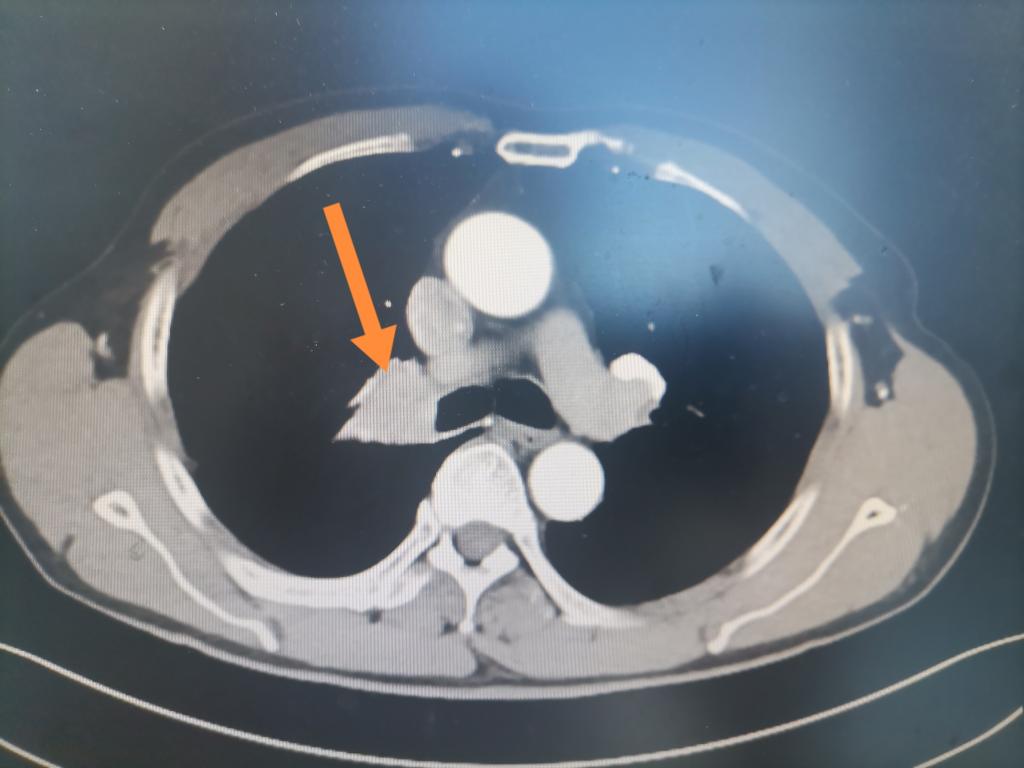

患者是一名68岁男性,因“痰中带血20余天”在我院呼吸科入院。入院后胸部增强CT:考虑右肺门占位并阻塞性炎症。组织病理检查提示为:肺鳞癌。明确具体性质后,我院迅速联系肿瘤科、放疗科、胸外科、呼吸科、病理科等科室,展开MDT,转入我院胸外科拟手术治疗。